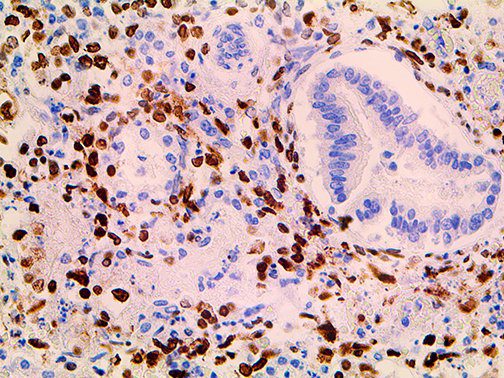

The first cytokines released are interleukin 1β (IL-1β) and tumor necrosis factor-α (TNF-α), which attract a variety of circulating white blood cells (WBCs) to the infection site, including neutrophils, monocytes, macrophages, and natural killer (NK) cells. This response, along with the antipathogenic chemicals released by these cells (i.e., complement), comprise the innate immune response. These cells directly attack the invading pathogen and also release additional cytokines, chief among them interleukin-1 and 6 (IL-6). IL-6 is essential for invoking the adaptive immune response, which calls T-cells, B-cells, and T helper (Th) cells to the infection site. IL-6 also stimulates further recruitment, proliferation and activation of macrophages.

It is the ICU physician who is most likely to witness one of the deadliest manifestations of the abnormal immunological response, the cytokine storm syndrome (CSS). This response is also referred to by some as the cytokine release syndrome (CRS). CSS is characterized by continuous activation and expansion of macrophage and lymphocyte populations, which secrete large amounts of cytokines, causing the cytokine storm. This massive cytokine release is akin to hemophagocytic lymphohistiocytosis (HLH) disease, a syndrome characterized by initial unchecked and persistent activation of cytotoxic T lymphocytes and NK cells.